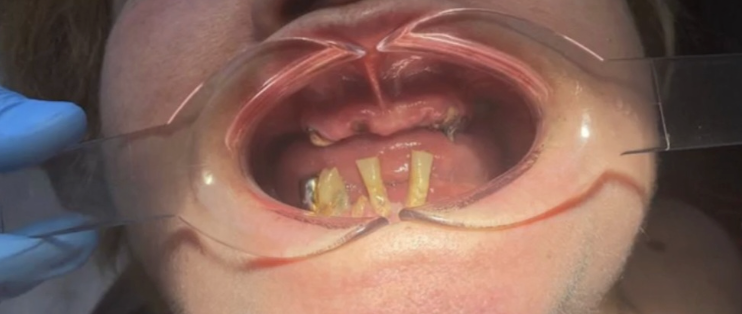

Врачи могли только удалить зубы и поставить мостовидный протез. Так и произошло.

Оказалось, что протез неудобный. Сложно разговаривать, портит дикцию. Много ограничений в питании, чтобы избежать поломки. При этом протез всё равно ломается!

После консультации мне сделали прицельные снимки челюсти — чтобы врачам стало понятно, с чем они имеют дело. На основе результатов обследования составили план лечения и озвучили точную стоимость.